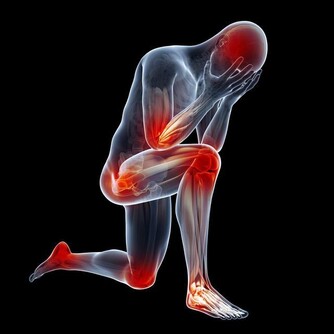

退化性膝關節炎並非老人家也開始找上了中壯年人,別以為這是喜愛登山或瘋馬拉松的後果,其實,久坐少動對膝關節的殺傷力更不容小覷。

現代人上班久坐,下了班上網、追劇、玩game,這些活動的共通點便是久坐,久坐已成為本世紀最大健康危機。一般人認為久坐對於骨關節危害主要在於腰痠背痛,殊不知,久坐對於膝關節的傷害並不亞於過度使用、體重過重或運動傷害,膝關節活動過猶不及,皆會導致退化性膝關節炎。

膝關節構造是由骨頭,即股骨、脛骨、髕骨,關節軟骨及軟組織,如關節滑囊、關節液及周圍肌肉韌帶構成,關節軟骨是否正常,以及關節液是否充足,都仰賴關節負重活動,如走、跑、跳等,幫助關節靈活順暢。

然而,久坐不但沒有讓關節承重,膝關節通常彎曲超過90度,此時膝關節壓力上升,生物力學的改變造成周邊韌帶張力過大,久而久之即可能發炎情況;此外,久坐不動易導致大腿肌力弱化,不足以穩定膝關節,更加速膝關節退化。